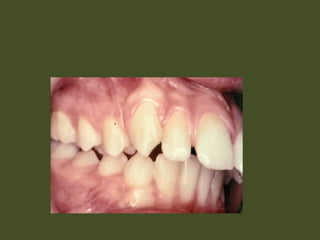

Class II, div 1 malocclusion

Class II, div 2 malocclusion

Class II, div1 malocclusion Class II, div 2 malocclusion